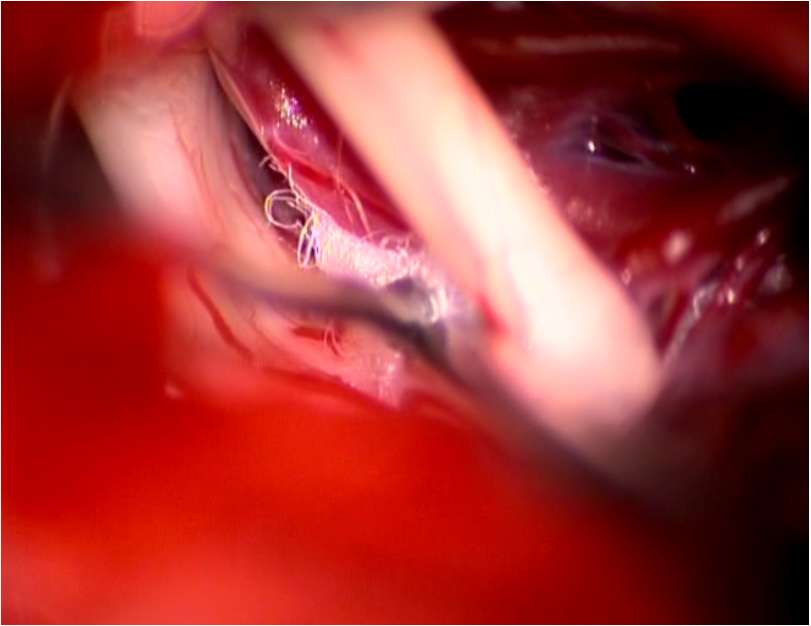

三叉神經(jīng)微血管減壓手術(shù)切口

術(shù)中顯微鏡鏡下神經(jīng)顯露